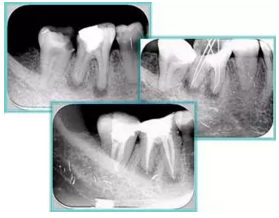

常見有修復(fù)性鈣化和增齡性鈣化。下面為根管鈣化 X 線片。

7. 器械折斷

右圖及下圖為器械折斷的 X 線片。箭頭處示折斷器械。

右圖箭頭處示臺階形成。